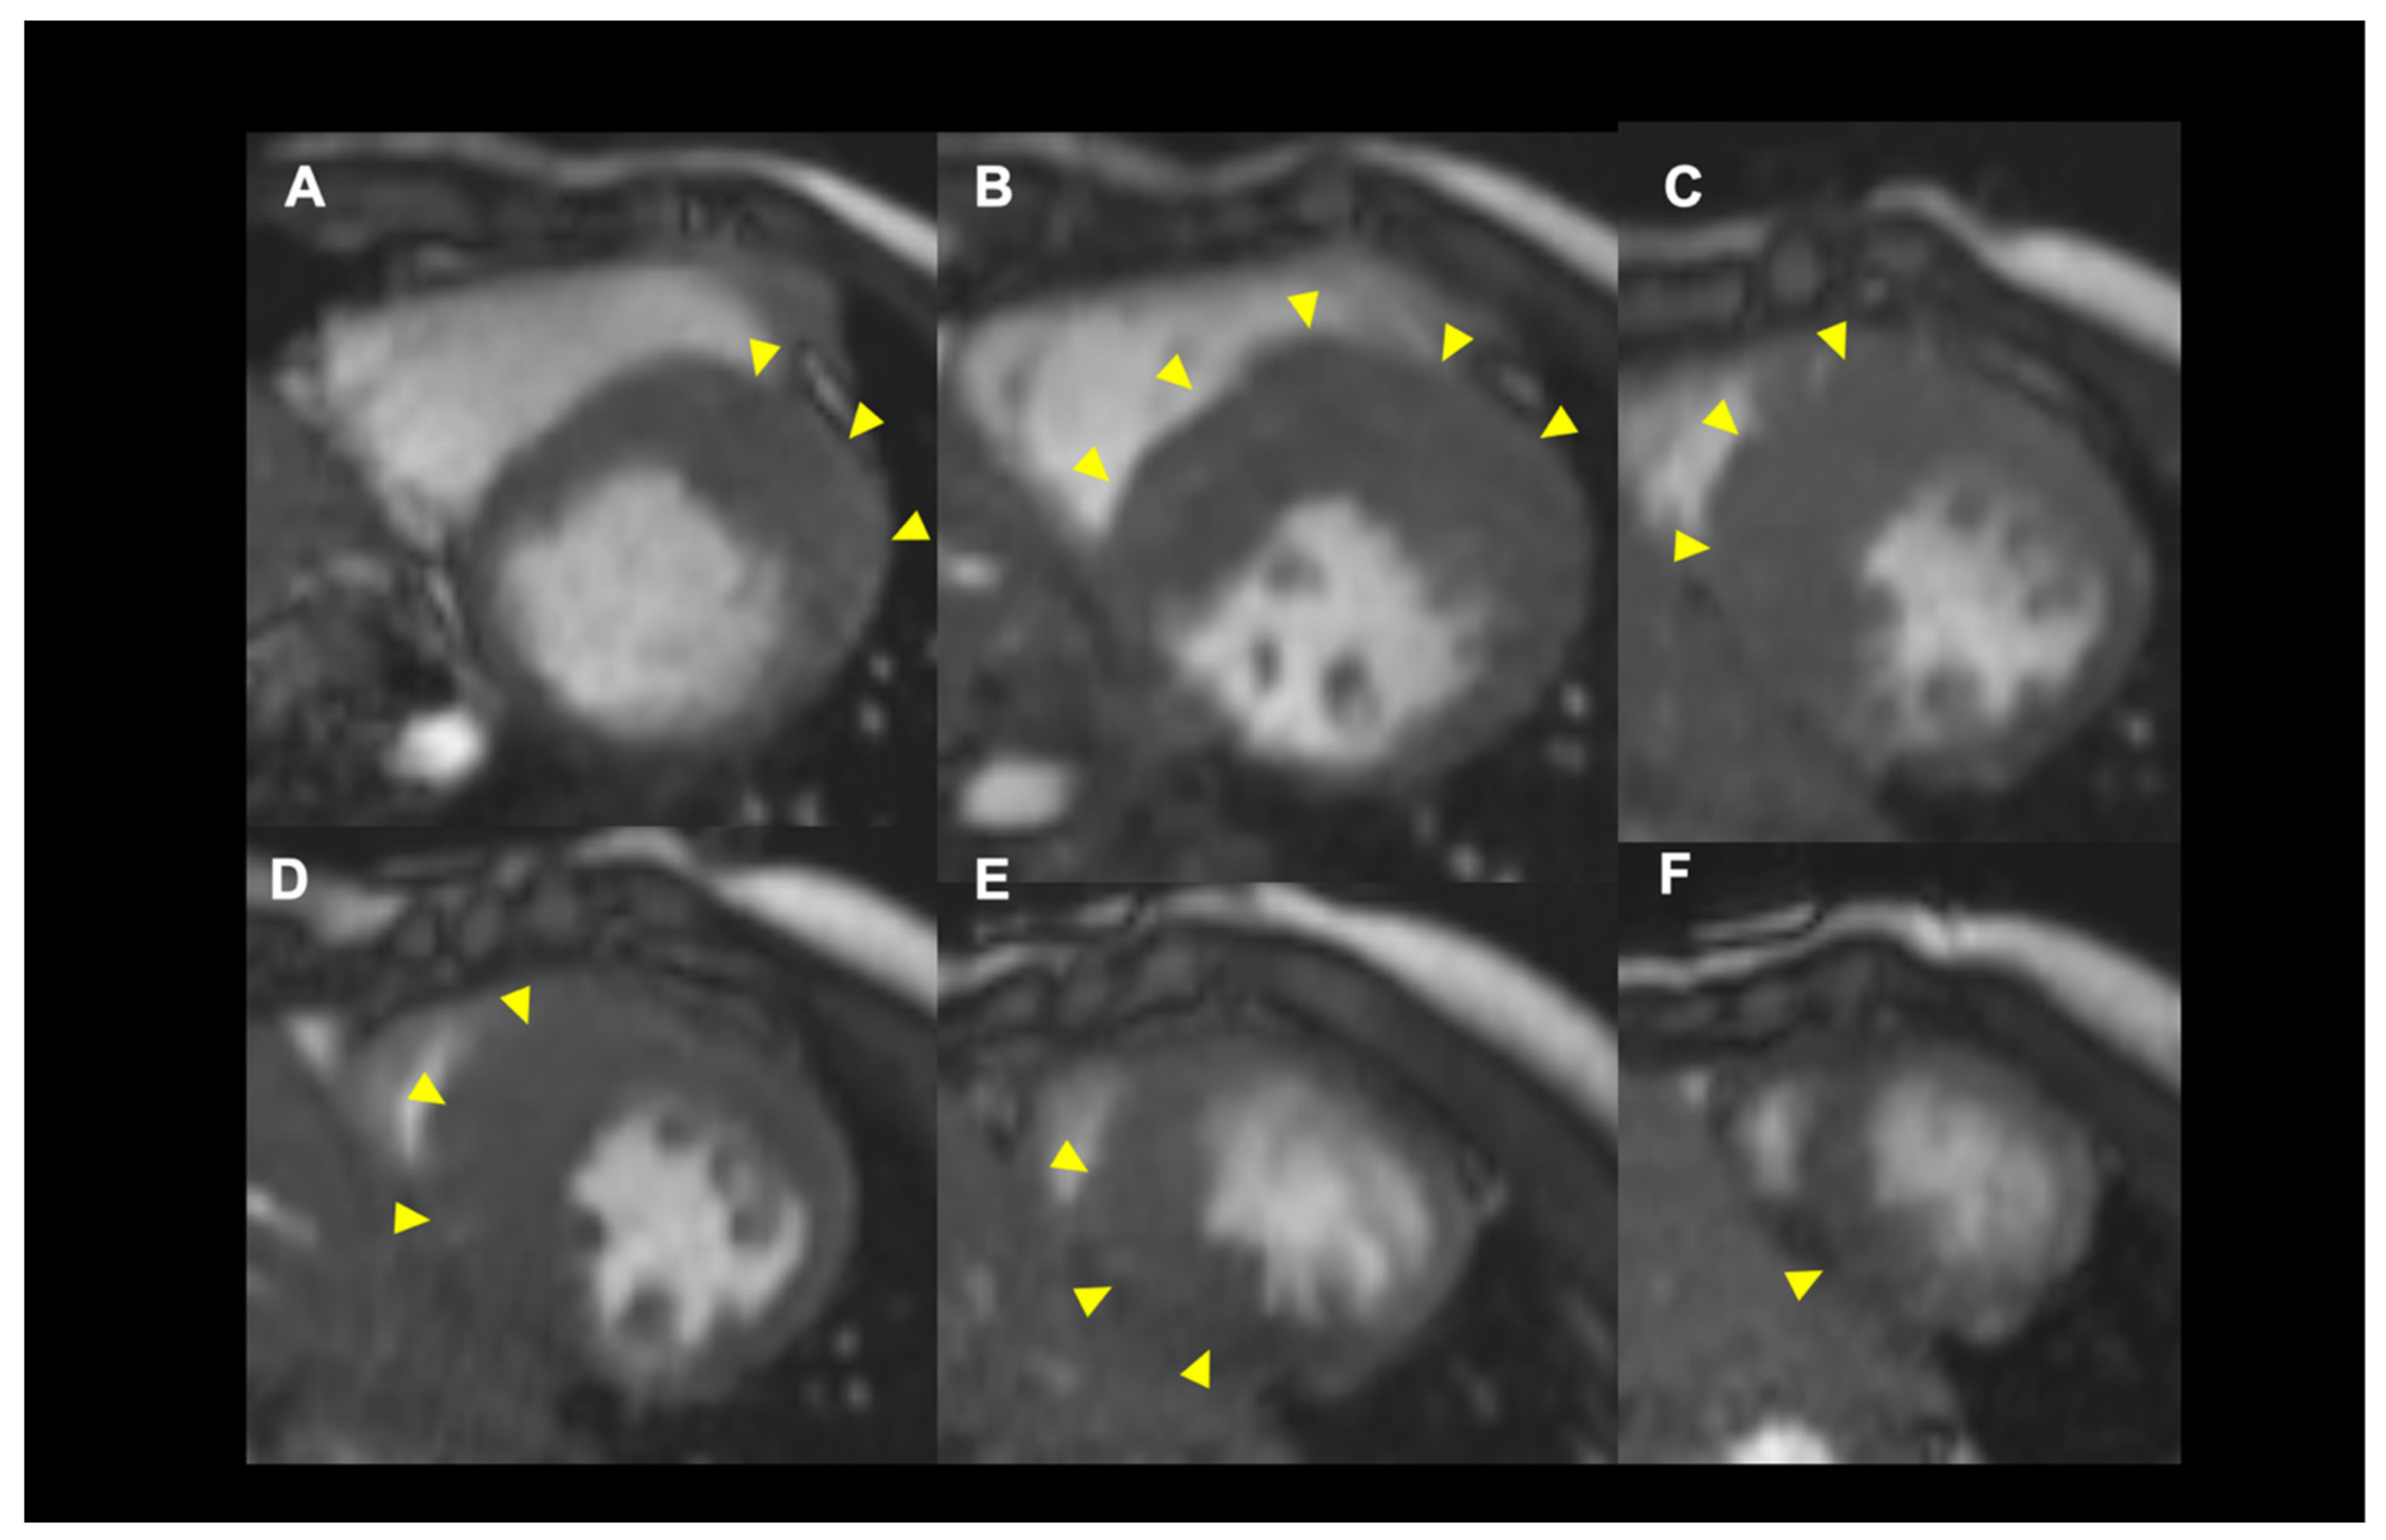

Assessment of LV Wall Hypertrophy

4.2. Role of Cardiac MRI for SCD Risk Stratification